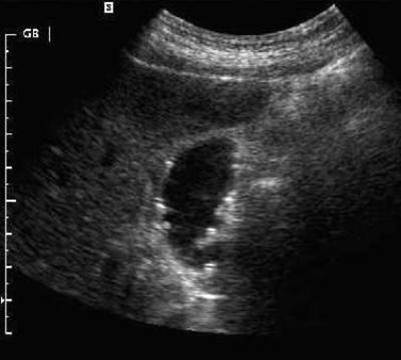

Cholelithiasis

Gangrenous Cholecystitis